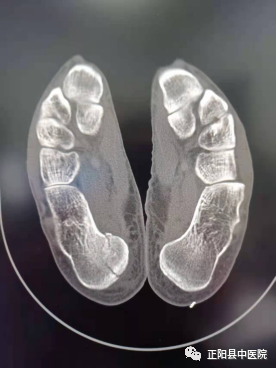

是不是所有的正侧位DR片搭配都能够给临床提供更多的信息呢?其实不然,在实际工作中我们还会遇到正侧位或侧轴位如此完美搭配,还依然不能诊断出来的外伤性骨折如下图。

这是一次夜班急诊中遇到的真实病例,跟骨侧轴位搭配如此完美,可是找不到异常征像,病人的足踝部肿胀非常明显,疼痛难忍。我们的外科医生经过与病人认真沟通后,做了一个64CT扫描,发现了跟骨的骨折。